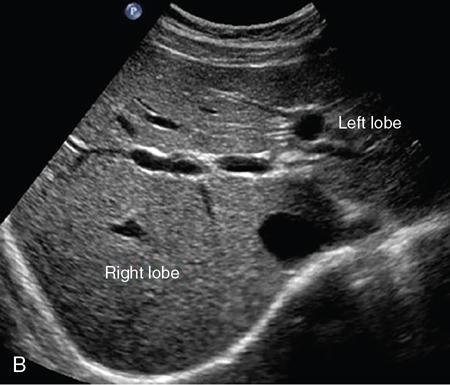

Samarjit Ghuman, Seema Sud, Deeksha Rastogi, Swapnil Sheth, T.B.S. Buxi PLAIN RADIOGRAPHY FOR HEPATOBILIARY IMAGING The diagnostic imaging techniques for hepatobiliary imaging can be intimidating with many techniques/modalities providing the information desired. The job of the diagnostic radiologist includes being familiar with the available choices and pick the ‘best fit’ keeping in mind the pros and cons of each modality, which includes plain X rays, Contrast studies using plain X rays and fluoroscopy, Ultrasound includiojng Doppler and Ultrasound elsastography, CT including multiphase CT and MRI and MRI elastography. Understanding the strengths and weaknesses of every modality as well as the ability to tailor each study individually will help to optimise patient cares. The abdominal radiograph is performed almost exclusively in the supine position and in the AP (anteroposterior) projection. In case of acute abdomen, an erect chest radiograph should also be performed to look for free air under the diaphragm. The standard abdominal radiograph should extend from the diaphragm to the inferior pubic rami, and includes the lateral abdominal wall musculature. Routinely no preparation is required for abdomen radiograph done for hepatobiliary imaging. The radiograph has limited soft-tissue contrast, however, the liver being the largest intra-abdominal organ, casts a perceptible shadow. The margins of the liver can indirectly be seen by outline of adjacent organs like lung, hemidiaphragm, pro-peritoneal fat line, kidney and gas shadows of stomach/colon. The right lobe is seen better than the left lobe of liver. The following pathologies may be visualized on the plain radiograph of the liver. Liver enlargement Liver mass Calcification Increased radiodensity of the liver Decreased radiodensity of the liver An ultrasound is the first line investigation; however, a radiograph may be done for routine evaluation of abdominal pain. The following pathologies may be seen on plain radiograph of the biliary tree. Calculi and Calcifications Gas ULTRASOUND OF HEPATOBILIARY SYSTEM Ultrasonography (USG) is the initial imaging modality of choice for scanning hepatobiliary system. USG is accurate and has high sensitivity and specificity in diagnosing biliary pathologies. Table 9.1.1 shows indications of ultrasound in hepatobiliary system. The real-time nature of ultrasound lends itself to demonstrate mobility of calculi and sludge and the sonographic Murphy sign can easily be elicited during scanning. The main disadvantage is operator dependence, patient’s body habitus, presence of gas which can obscure the visualization of organs, overlying bandages in a postoperative patient and incomplete evaluation in a nonfasting state. USG of upper abdomen should be done after 6–8 hours of overnight fasting. Milk and fatty food should be avoided as they cause contraction of the GB and may cause the GB walls to appear thickened. History of previous surgery, especially cholecystectomy should be elicited. The patient may be positioned in supine or left lateral decubitus position. The GB can be scanned from a high/lateral view, looking through the ribs in supine position or through a sub-costal view in left lateral decubitus position. Position of patient may be changed to demonstrate mobility of structures. The GB is an anechoic structure which is located in the GB fossa along the posterior and inferior aspect of the liver. It has a fundus, body and a neck. It should always be examined in at least two planes (Fig. 9.1.6A and B). The wall of the normal GB should measure 3 mm or less and pathological GB wall thickening can be due to cholecystitis or a neoplastic aetiology. Calculi appear as mobile hyperechoic foci, with distal acoustic shadowing. Other pathologies include polyps and sludge which can be differentiated on the basis of their mobility. The CBD measures less than 6 mm in diameter with increase in the diameter with patient’s age and after cholecystectomy. The CBD is usually scanned in an oblique subcostal plane with the patient in the left decubitus position (Fig. 9.1.7). Dilatation of the intrahepatic biliary radicles is readily assessed with USG and normal intrahepatic biliary radicles are usually not appreciated on USG. Ultrasound of the liver, broadly, is done to assess the size, surface (smooth, coarse or lobulated) parenchymal echogenicity (increased or decreased) vascularity and for presence and evaluation of intrahepatic masses or fluid collections. The liver is divided into right and left lobes by plane of middle hepatic vein which passes through GB fossa and notch of IVC (Cantlie Line). Couinauds classification is the most commonly used system for liver segmental anatomy and described liver into eight functional segments. It is based on distribution of portal and hepatic veins. Every segment has its branch from portal vein, hepatic artery and bile duct (Fig. 9.1.8). Curvilinear transducer (3–5 MHz) is used for routine examination of liver and GB (Fig. 9.1.9). A high-frequency linear transducer (9–11 MHz) (Fig. 9.1.10) can be used to look for subtle irregularity of the liver surface for early Cirrhosis and fine details of GB wall. The liver is scanned in deep inspiration, which causes inferior movement of liver, so that superior borders of the liver are well visualized. Supine position is used for the size of the liver. The measurement is made in sagittal mid clavicular position on right side, in craniocaudal dimension. It is taken from diaphragm to the lower end of the liver. It should be <16 cm and varies with age and sex. The liver is divided into four vertical sectors by three hepatic veins and plane of bifurcation of portal vein divides these 4 sectors in to 8 segments. The right hepatic vein creates vertical plane in the right lobe separating segments V and VIII (anterior) from VI and VII (posterior). The portal vein bifurcation creates a transverse plane and divides these segments into superior (VII, VIII) and inferior segments (V, VI). The left hepatic vein divides the left lobe into medial (IVa, IVb) and lateral sectors (II, III). The left portal vein divides left lobe into superior (Iva, II) and inferior segments (III, IVb). The middle hepatic vein separates medial segments of left lobe (IVa, IVb) from anterior segments of right lobe (V, VIII). Ligamentum teres separates segment III from IVb. Ligamentum venosum separates segment I from IV and II. Cystic duct is an anechoic tubular structure which connects neck of the GB to the extrahepatic biliary tree. In long axis view of GB, the neck of the GB is related to main lobar fissure which appears as a linear echogenic line which runs obliquely between neck of GB and right portal vein. In the right oblique sub coastal view CBD is seen anterior and parallel to portal vein. A series of standardized sections or views may be obtained for liver scanning. Transverse Subcostal View: In this view the probe is angled cephalic and placed transversely under the ribs on the right side and portions both lobes of the liver can be seen (Fig. 9.1.11). Mid Transverse View (Fig. 9.1.12) in this transducer is kept in transverse plane in the midline below the xiphisternum. It visualises the liver in an inferior to superior transverse oblique plane and portions of both lobes of liver can be seen along with right and left portal veins. This view is obtained by angling the transducer superiorly toward the hepatic venous confluence. In this view, we can see the three hepatic veins joining the IVC. Right Parasagittal View for Both Right Lobe and Kidney: This view allows assessment of inferior right lobe of liver. It also allows assessment of relative echogenicity of liver and renal cortex as both are seen together in the same image. Normal liver parenchymal echogenicity is greater than renal cortex and less that renal medulla (Fig. 9.1.14). Parasagittal Right MidClavicular View: In this transducer is kept in sagittal plane in right midclavicular line, and oriented supero-inferiorly. This is the standard view for assessing craniocaudal span of liver (Fig. 9.1.15). Parasagittal View for the Left Lobe: For evaluation of left lobe of liver and lateral segments (2 and 3) (Fig. 9.1.16). This view is obtained along the direction of the main portal vein. CEUS of the liver is done to evaluate Focal Liver Lesions and complements traditional B mode ultrasound and Doppler study. It is a simple, accurate and cost-effective tool complimenting indeterminate CT and MRI findings or for characterization of lesions in patients who cannot receive CT/MRI contrast and can be used in patients with compromised renal function, with minuscule risk of side effects. As CEUS is real-time, microvasculature can be studied along with tissue perfusion kinetics. Indications and uses of CEUS: Contrast agents and technique: Interpretation: Contrast-enhanced ultrasound of a hepatic hemangioma in different phases (Fig. 9.1.19). Limitations of CEUS: Liver elastography is a noninvasive method for diagnosing liver fibrosis. Liver fibrosis is induced by chronic liver disease leading to cirrhosis and liver cancer. Liver biopsy is the gold standard for diagnosing the degree of fibrosis and for staging but it is an invasive method. Elastography helps in analysing the elasticity or the stiffness of the tissue. A stiffer liver tissue indicates fibrosis or chronic liver disease. ARFI is based on the principle of measuring Shear wave velocity. Short duration acoustic pulses which are generated in the tissue and these give rise to shear waves which travel, perpendicular to the ultrasound beam. These shear waves cause tissue displacement followed by recovery. This displacement and recovery depend on tissue stiffness. To monitor these shear waves US beams of low intensity are emitted continuously parallel to the main beam along with the push pulses, and these beams can gather data regarding the tissue stiffness. The shear waves cause tissue displacement and this tissue then recovers from the impulse. From this data the degree of tissue stiffness can be obtained which is displayed either as a map or quantitatively where tissue elasticity is expressed as shear wave velocity measured in meters per second. F0, normal; F1, enlarged fibrotic portal tract; F2, periportal/initial porto-portal septa with intact architecture; F3, architectural distortion with no obvious cirrhosis; F4, cirrhosis. It is also known as Transient Elastography (TE) and works on the similar principle as ARFI, the difference being that B mode ultrasound image is not produced. DOPPLER OF PORTAL VEIN The portal vein divides at the portahepatis into right and left branches. The right portal vein divides into anterior and posterior branches, and the left portal vein divides into medial and lateral branches. Portal vein shows a continuous, forward low-velocity flow (15–28 cm/s) on colour Doppler scanning. The flow is hepatopetal, that is, towards liver and is red in colour as it is flowing towards the transducer. It has an undulating pattern and shows respiratory variation with increase flow in inspiration. It may reflect cardiac variation and shows postprandial increase calibre and flow in healthy individuals. Normal Doppler waveform of portal vein (Fig. 9.1.22). Portal hypertension can be defined as elevated pressure within the portal venous system resulting in impaired blood flow through the liver. INTRAOPERATIVE PANCREATIC AND HEPATIC ULTRASOUND Intraoperative ultrasonography of the pancreas was first described in 1980 by Lane and Glazer. It is an important technique for guidance of both open and laparoscopic surgical procedures of the pancreas. As the transducer is in direct contact with the organ of interest, with no interference with air of adjacent soft tissue, it provides good resolution. It is considered superior to CT and MRI in assessing the intraoperative tumour resectability and vascular invasion and guiding resection. Indications and uses For intraoperative US during open surgical procedures, a high-frequency linear-array transducer or the hockey stick transducer (Fig. 9.1.23) are used which create high-resolution detail of the exposed pancreas. The side-fire curved linear-array transducer is effective for obtaining a wider view of the pancreas and its surrounding structures and for scanning the liver. Intraoperative hepatic ultrasound gives the real-time visualization of the hepatic anatomy and aid for surgical planning and making decision during surgery. Indications and uses Transducer and technique Limitations MULTIDETECTOR CT OF THE HEPATOBILIARY SYSTEM AND CHOLANGIOGRAPHY The cross-sectional plane of the patient is denoted as the x/y plane. The plane along which the table moves is the ‘z’ plane. Multidetector CT denotes more than one detector along the Z-axis, with the latest machines having up to 320 and now even 640 rows of detectors. This provides CT with very fast, high resolution, isotropic images which can be reconstructed in any plane or even curved planes. MDCT scanners can comfortably scan the entire abdomen in 10 seconds or less, thereby allowing visualization of different phases of contrast enhancement. Contrast Media (CM) after administration gets distributed from the intravascular compartment into the interstitial spaces. Intravascular arterial enhancement (for angiography) and parenchymal enhancement have different kinetics. Parenchymal enhancement is directly proportional to total iodine dose being administered and inversely proportional to weight, which is a marker of extracellular volume into which contrast redistributes. Rate of iodine administration has no effect on degree of parenchymal enhancement. As a general rule approx. 500–600 mg of iodine/kg body weight achieves adequate hepatic parenchymal enhancement. For a 60 kg adult, this translates into approx. 100–120 mL of contrast containing 300 mg of iodine per mL. Intravascular or arterial enhancement is controlled by rate at which iodine is administered (flow rate and iodine concentration of CM) iodine flux and duration for which contrast is administered longer injection also leads to better overall arterial opacification due to recirculation effects. This principle is made use of while performing abdominal CT Angiography. Higher iodine delivery rate per unit time using a higher iodine concentration contrast medium also improves conspicuity of vessels and hypervascular lesions such as HCC. For identical parameters, difference in arterial enhancement between patients is dependent on cardiac output with enhancement being inversely proportional to cardiac output. For optimal imaging and enhancement, in multiphase imaging and angiographic studies, contrast material administration and parenchymal or vascular enhancement must be synchronized with CT data acquisition. The two main methods are: Test bolus technique: A test dose of contrast is given and the time to peak enhancement is measured in a ROI placed in a target vessel this information can be used to tailor CT acquisition. Automated bolus Triggering: ROI is placed in target vessel (usually aorta at level of diaphragm) on a plain image. While CM is injected, a series of low dose scans is obtained through the ROI. When the density of contrast reaches a predefined threshold (e.g. 150 HU), at time ‘t’ the scan is automatically triggered. The trigger delay after time ‘t’ is a minimum of 2 sec, and can be programmed to any value. Bolus tracking is nowadays the method of choice for planning contrast medium administration and this technique provides more homogenous opacification. Saline chase is recommended in all multiphase protocols. Significant amount of contrast may be present in the peripheral veins after injection of IV contrast and use of saline chaser leads to better vascular enhancement and lower overall contrast dose (Fig. 9.1.24). Using the above, a standard sequence of acquisitions and contrast enhancement techniques can be tailored to the pathology and organ of interest and pre-programmed into the scanner menu, which includes kVp, mAs, pitch, rotation time, slice thickness etc. This is known as a scan protocol. However, these can be modified as necessary. For example, rotation time can be shortened and pitch can be increased for breathless patients to reduce scan times (Table 9.1.4). Multidetector CT is the workhorse of hepatobiliary imaging. It plays a major role in imaging congenital, traumatic, infective, neoplastic and vascular pathologies of the hepatobiliary system. Scans can be obtained with or without intravenous (IV) iodinated contrast material administration. Multidetector CT scanners are capable of imaging multiple phases at different points of time following injection of contrast and provide dynamic imaging due to fast scan times and rapid coverage of the abdomen. Indications for liver imaging include, but are not limited to: Unenhanced Scan: Hepatic fat estimation, radio opaque biliary calculi. Single Phase Scans: Liver abscess, polytrauma, follow up of known oncologic or benign lesions, abdominal pain, suspected cholecystitis. Multiphase Studies: Evaluation of hepatic masses, imaging in cirrhosis, imaging for resectability, liver donor evaluation, malignancy of GB, hepatic venous outflow obstruction etc. CT Angiography of Hepatic Vessels: Trauma, vasculitis, post-operative bleeding and as a part of multiphase studies. Depending on the indication, scanning protocols can be tailored to highlight the suspected pathology and provide relevant answers for further management (Table 9.1.5). The liver has a dual blood supply, most of which is derived from the portal vein. After injection of contrast, until the portal vein provides recirculated contrast material filled blood to enhance the hepatic parenchyma, the hepatic parenchymal enhancement is relatively poor and dependent only on the hepatic artery. The hepatic arterial phase can be divided into an early arterial phase without any portal opacification, a late arterial or portal inflow phase in which there is some portal vein opacification. This is followed by a portal venous phase in which portal and hepatic veins are enhanced (also called the hepatic venous phase in some articles). In addition, an unenhanced/plain scan and an equilibrium phase can also be acquired. Tumour conspicuity of hypervascular lesions was found to be best on the late arterial or portal inflow phase (Fig. 9.1.25). The early arterial phase is seen up to 10 seconds after trigger, and provides ‘angiographic’ images of hepatic arterial anatomy. This phase is used to provide details regarding arterial anatomy and morphology. Later arterial phase 18–23 seconds, portal venous phase 60–70 seconds and equilibrium phase 180 seconds are obtained after trigger. Equilibrium phase images have been shown to increase detection of hepatocellular carcinoma in cirrhotic patients. The portal venous phase is the standard phase for routine chest/abdomen survey and follow up of hepatic abscesses and hypovascular metastases. Single Phase Scan Protocol: Oncologic follow-up, Liver Abscess – For routine single-phase CT, contrast as per body weight can be injected over 40 seconds and scanning can be done after an empiric delay of 70 seconds from the beginning of injection. This protocol provides good parenchymal enhancement and portal and hepatic vein visualization. Plain scan is optional. Dual-Phase Scan Protocol: Hepatic evaluation in patients with malignancies known to have hypervascular metastases – Neuroendocrine tumours, renal cell carcinoma, thyroid carcinoma, (.) melanoma etc. Late arterial Phase 20–22 seconds and Portal venous phase at 60–70. Plain scan optional. Hepatic Resection Protocol: For patients with known hepatic mass being evaluated for resection. Early arterial phase provides pure arterial or angiographic images. It is obtained at 8–10 seconds post trigger followed by portal venous phase at 60–70 seconds. This is required for arterial and venous anatomy and volumetric evaluation if required. Plain scan is not required. In case a hepatic mass needs characterization as well as resectability planning, late arterial and equilibrium scans may also be done. Indications for angiography are further discussed in the section on angiography. The same biphasic protocol using angiography or arterial phase images is used in patients with trauma suspected to have pseudoaneurysms, hepatic artery thrombosis or dissection in transplant recipients, evaluation of living donors and in patients in whom an angiographic ‘road map’ is required prior to intervention. Triphasic or 4 phase scan Protocol: Standard of care for patients with cirrhosis being evaluated for Hepatocellular carcinoma and for patients being evaluated for hepatic mass of uncertain aetiology. Late arterial phase scan: 20–22 seconds, Portal venous scan at 60–70 seconds and Equilibrium scan at 180 seconds. Plains scans are optional. Our institutional practice is to always do plain scans in patients who have undergone hepatic intervention. Plain scans also help to visualize siderotic and steatotic nodules. A further delayed scan is suggested by some authors at 10–15 minutes for characterization of hepatic masses of uncertain provenance. This is particularly useful in cholangiocarcinoma (Table 9.1.6).